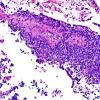

1A7A HPAP (Case 1) H&E 20X 6

1A7B HPAP (Case 1) H&E 40X 3

1A8 HPAP (Case 1) H&E 20X 9

1A9 HPAP (Case 1) H&E 20X 10

1B1 HGAP (Case 1) H&E 10X 10

1B1 HPAP (Case 1) H&E 10X 8A

1B2 HGAP (Case 1) H&E 20X 9

1B2 HPAP (Case 1) H&E 20X 3